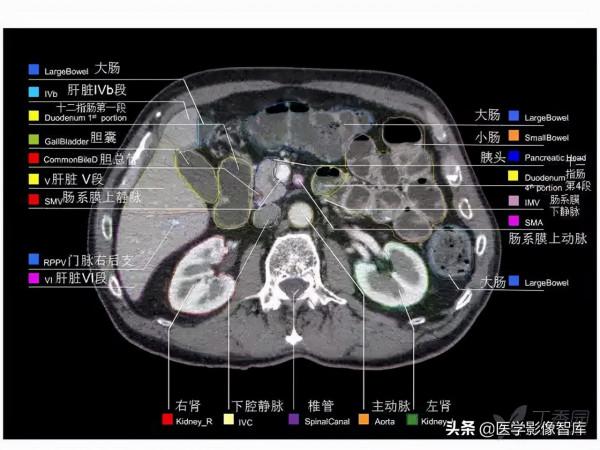

腹部CT